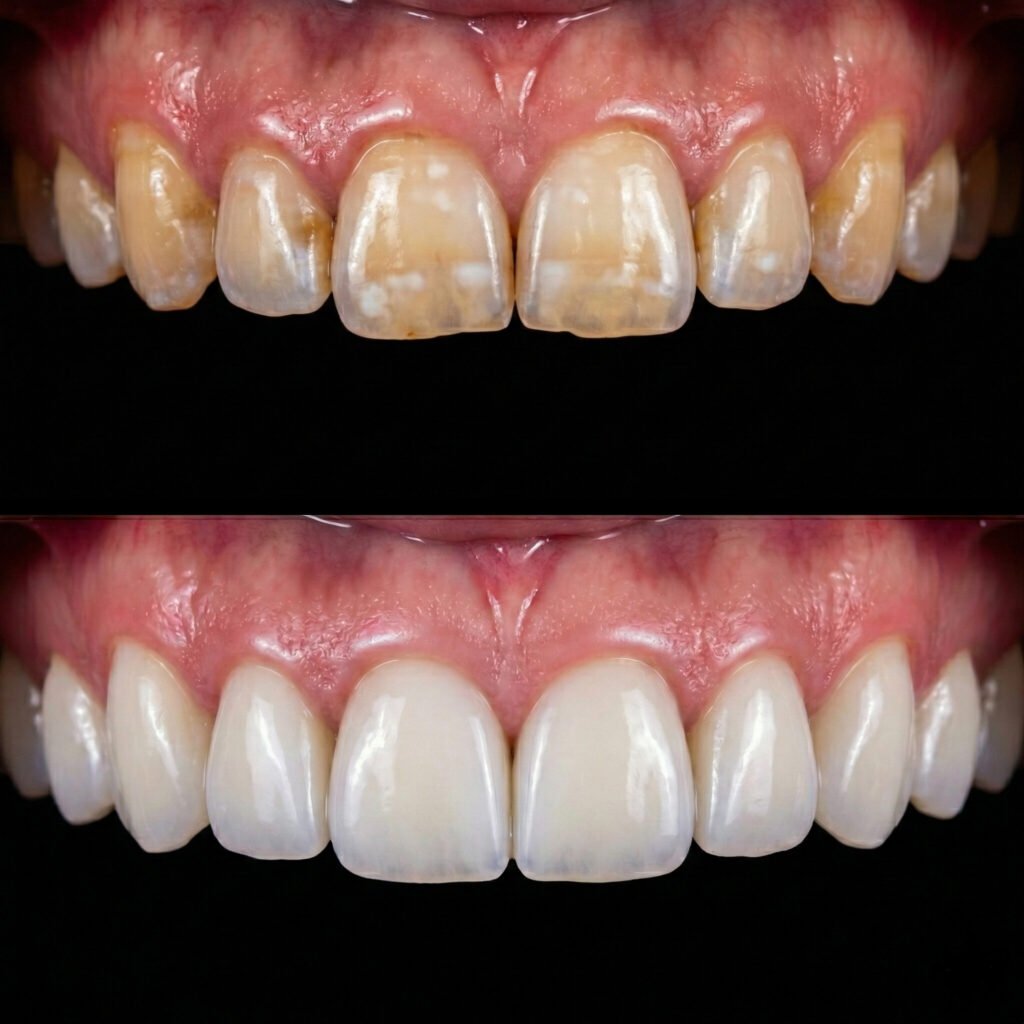

hollywood smile agadir

Hollywood Smile

Un relooking Hollywood Smile sur mesure pour un sourire lumineux, harmonieux et sophistiqué.

facettes dentaires agadir

Facettes Dentaires

Transformez votre sourire en toute confiance avec des facettes dentaires adaptées à vos besoins.